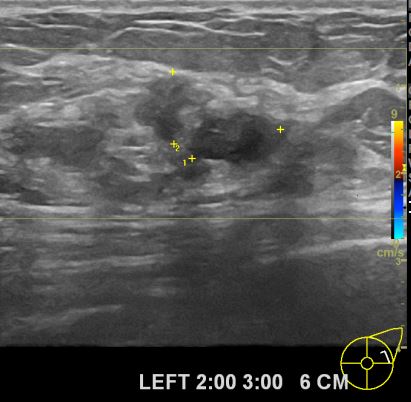

상기환자 건강검진후 이상소견으로 정밀한검사권유 받아 내원한 60대여성분으로

좌측유방의 의심스러운 멍울 조직검사 시행후 유방암 진단되었읍니다